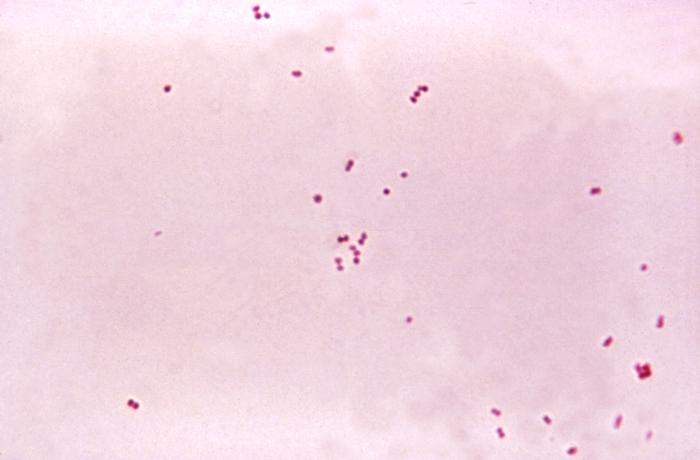

The causative organism may be identified by gram stain, polymerase chain reaction (PCR), Matrix Assisted Laser Desorption/Ionization – Time of Flight (MALDI-TOF), and culture.

Bacterial Meningitis

- Increased neutrophils

- Decreased glucose